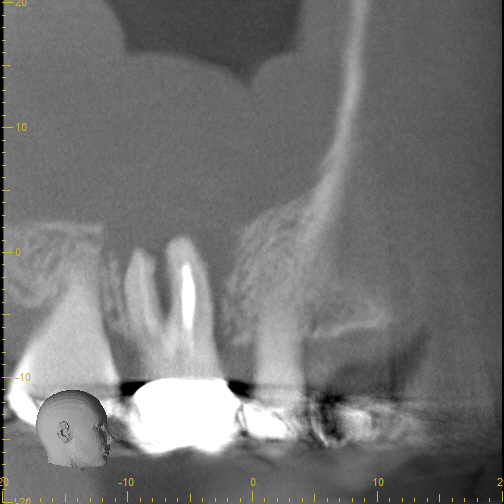

3_pre CBCT

8_recall 1 yr CBCT

Case 7

These images are from a 3D scan and show how important is a correct diagnosis. The pre-treatment image on the left shows what looks like two teeth with infections, but thorough testing showed that only one tooth needed treatment. The right image shows complete healing--around both teeth-- one year later. A careful diagnosis resulted in saving the adjacent tooth from unneeded treatment.